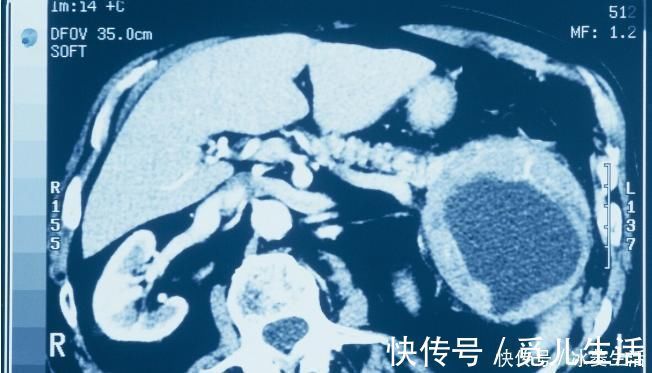

之前有一位年轻的胰腺癌患者,才三十多岁,本来觉得自己还有很长的一段要走,还有很多的事情要去做,谁知医生却宣布她的生存期只有一年左右,听到这个消息全家人都非常悲痛,可她很快就调整了心态,到现在已经十二年过去了,她还生活的非常好,肿瘤也没有继续发展的趋势。

出现这样好的结果与正确的治疗有很大关系,但同时也与她的乐观心态、强大意志密不可分,她在患癌后很坚强,没有悲痛欲绝,没有怨天尤人,而是摆正心态、积极面对。的确,癌症治疗中患者的心态、意志很关键,甚至有时候能超过药物的功效。